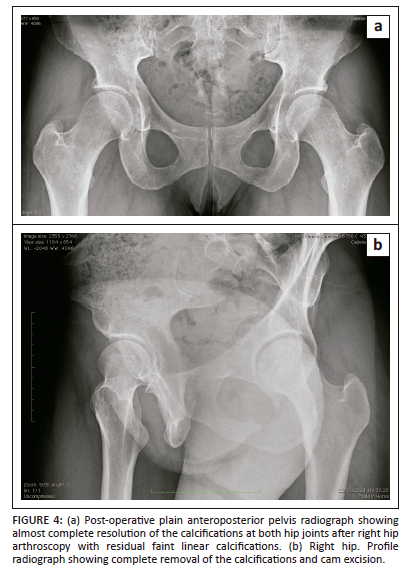

The patient was discharged the next day and adhered to the standard postoperative recovery process for labral repair and osteochondroplasty. This involved using crutches for 3 weeks, performing circumduction movements, and using a stationary bicycle for rehabilitation. The patient had no postoperative complications and received heterotopic ossification prophylaxis (Naproxen 500 mg twice daily) after the procedure for 3 weeks. At the outpatient follow-up visit 3 months after surgery, plain radiographs (Figure 4a and b) revealed almost complete disappearance of the previously observed calcifications in the right hip and surprisingly, spontaneous resolution in the untreated left hip with faint linear residual calcification bilaterally. At the 1-year follow-up, there was no recurrence of the ossifications, and the symptoms had completely resolved. Her MHHS was 92, her HOS-ADL score was 93, and her HOS-SS score was 92.